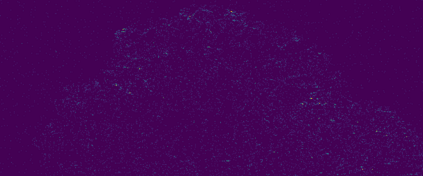

The usage of chemical imaging technologies is becoming a routine accompaniment to traditional methods in pathology. Significant technological advances have developed these next generation techniques to provide rich, spatially resolved, multidimensional chemical images. The rise of digital pathology has significantly enhanced the synergy of these imaging modalities with optical microscopy and immunohistochemistry, enhancing our understanding of the biological mechanisms and progression of diseases. Techniques such as imaging mass cytometry provide labelled multidimensional (multiplex) images of specific components used in conjunction with digital pathology techniques. These powerful techniques generate a wealth of high dimensional data that create significant challenges in data analysis. Unsupervised methods such as clustering are an attractive way to analyse these data, however, they require the selection of parameters such as the number of clusters. Here we propose a methodology to estimate the number of clusters in an automatic data-driven manner using a deep sparse autoencoder to embed the data into a lower dimensional space. We compute the density of regions in the embedded space, the majority of which are empty, enabling the high density regions to be detected as outliers and provide an estimate for the number of clusters. This framework provides a fully unsupervised and data-driven method to analyse multidimensional data. In this work we demonstrate our method using 45 multiplex imaging mass cytometry datasets. Moreover, our model is trained using only one of the datasets and the learned embedding is applied to the remaining 44 images providing an efficient process for data analysis. Finally, we demonstrate the high computational efficiency of our method which is two orders of magnitude faster than estimating via computing the sum squared distances as a function of cluster number.